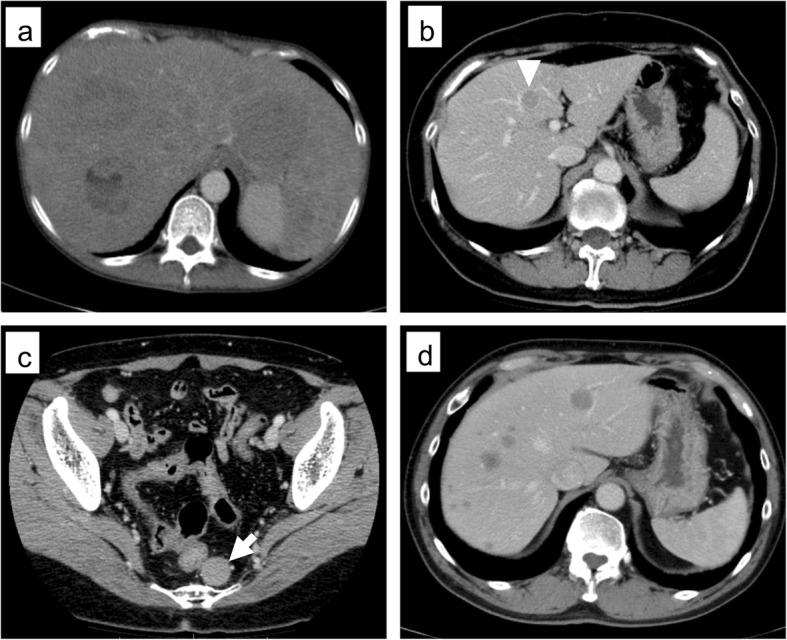

Here, we report three cases of metachronous liver metastasis after long-term follow-up of endoscopic mucosal resection (EMR) for rectal NEN. The pathological findings indicated a depth lower than the submucosa and complete radical resection in all cases and lymphovascular invasion in only one case. All three cases showed metachronous multiple liver metastases after 9-13 years of follow-up for EMR, despite achieving complete resection and without muscular invasion.

在此,我们报告3例直肠NEN内镜黏膜切除术(EMR)长期随访后发生异时性肝转移的病例。病理结果显示所有病例浸润深度均低于黏膜下层且均实现了根治性完全切除,仅1例有脉管侵犯。尽管3例均实现了完全切除且无肌层侵犯,但在EMR术后9 - 13年的随访中均出现了异时性多发肝转移。